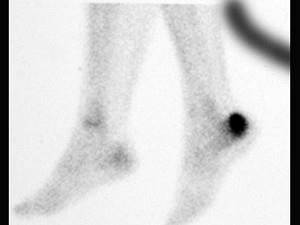

女,48岁,長跑运动员,左跟骨部痛,结合图像,最可能的诊断是 ( )A、左踝关节退行性变B、应力性骨折C、左跟骨骨髄炎D、结核...

问题 女,48岁,長跑运动员,左跟骨部痛,结合图像,最可能的诊断是 ( )

选项 A、左踝关节退行性变 B、应力性骨折 C、左跟骨骨髄炎 D、结核 E、未见异常

答案 B